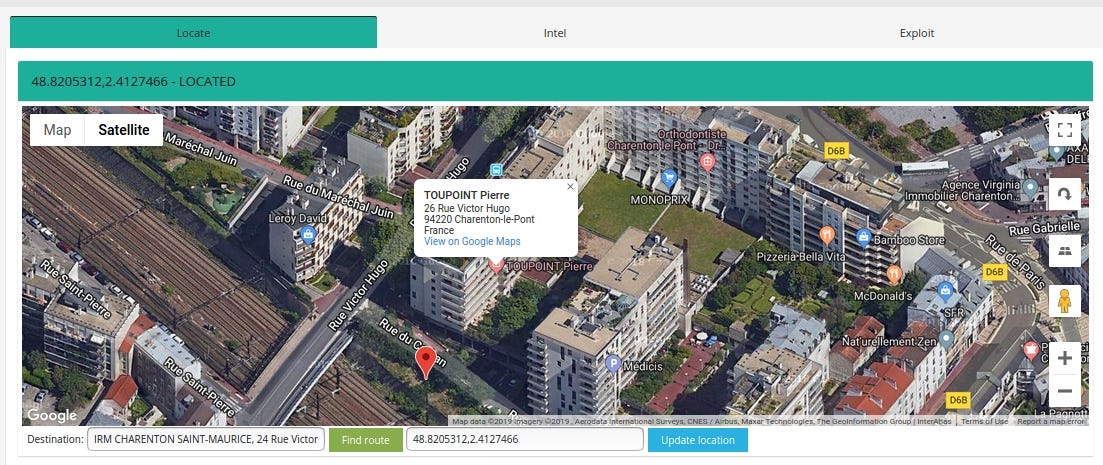

Case #2 IRM CHARENTON ST MAURICE, 22 rue Victor HUGO 94220, CHARENTON LE PONT

Medecon Clipper is web server designed to make images and reports available for the general practitioners or the specialists.

Query: http.favicon.hash:-897903496

Some devices/EMRs/software are used only in specific countries. Medecom (http://www.medecom.fr/) is a French based company and most of it are exposed in France.

Medcon Clipper reveals precise location in HTML content

IP location points to Montmorency but the actual clinic is located in suburbs of France

In addition, it shows the current version of software — 4.4. The newest one is 4.10, so it hasn’t been updated for a while.